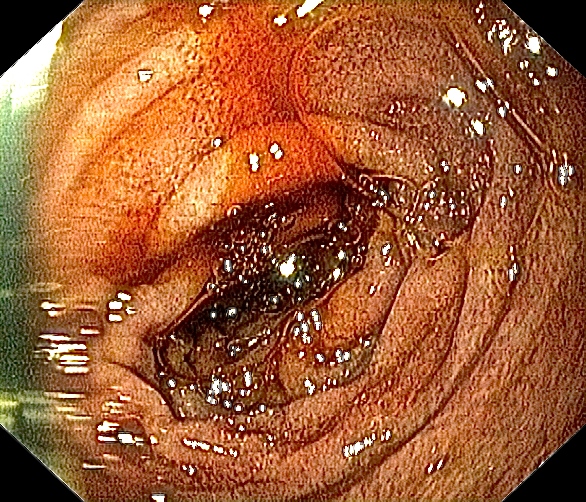

Inngang til tolvfingertarmen. Salvador Dali – go home! 🙂

Ved tolvfingertarmen kommer galle ut feil vei. Rene rundkjøringa 🙂